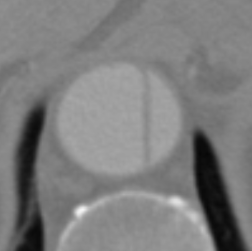

Figure 9 shows axial CTA images of an aortic dissection case. In both rows of this figure an example for executing an inpainting with the inpainting tool is given. The image section of all sub-figures is equal to the defined region of interest. The sub-figures in Figure 9 show from left to right: unedited CTA scan showing the aorta and surroundings, the mask used for the inpainting and the inpainting result. The Sub-images (a) and (b) include a dissected aorta, whereas the dissection is removed in the sub-images (d) and (f).

(a) Original image

(b) Masked image

(c) Inpainting result

Figure 9: Two examples for an inpainting of an aortic dissection utilizing the inpainting tool.

Looking at the results presented in Figure 9, one can see that the depicted dissected aorta is successfully changed to a healthy looking aorta. But it is also noticeable, that the region reconstructed by the inpainting is slightly blurred, which could be addressed by refinement of the EdgeConnect model. The timing analysis in section 6 shows that a call of the inpainting tool is completing in around four seconds, wherein the majority is caused by executing the neural network. This indicates the code of the inpainting tool itself offers little room for speeding up the application.